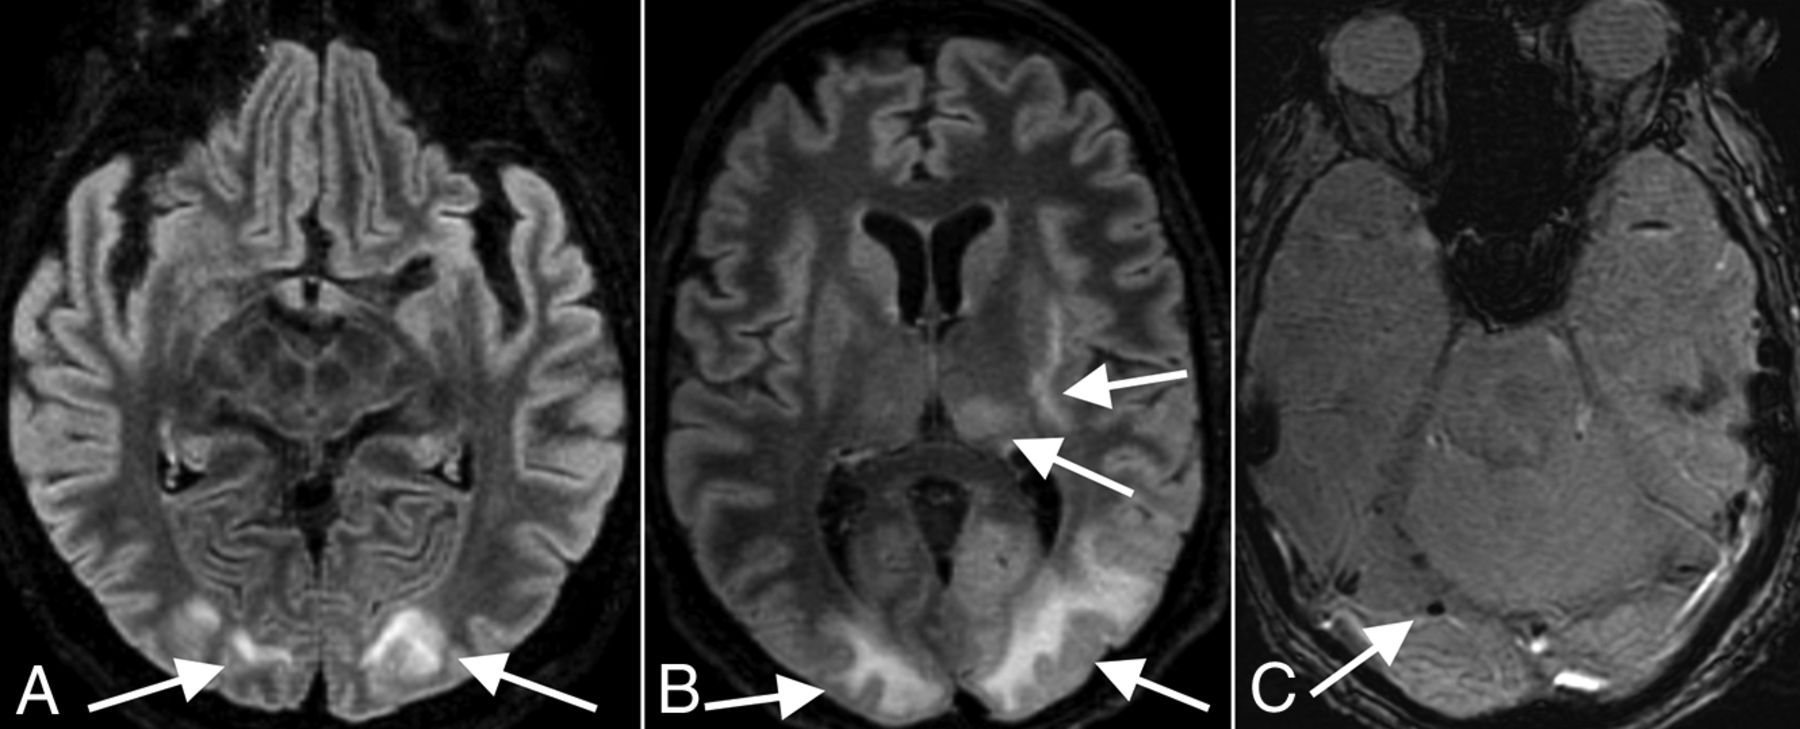

There were 3 patients with imaging findings typical of PRES, with acute development of occipital subcortical white matter edema. One patient, a 72-year-old man, was diagnosed solely on the basis of the CT examination. He was intubated for hypoxic respiratory failure and also developed acute kidney injury. The patient was initially hypotensive, requiring pressors, but afterward was intermittently hypertensive. He had follow-up CT showing resolution of occipital white matter edema. The other 2 patients, a 65-year-old woman (Fig 3A) and a 63-year-old man (Fig 3B, -C), both underwent CT and MR imaging and had evidence of associated acute microhemorrhage on susceptibility-weighted MR imaging sequences. Both of these patients also had complications of hypoxic respiratory failure requiring intubation, acute renal failure, and acute hypertension. The 65-year-old woman did not have follow-up imaging, but the 63-year-old man had follow-up CT showing resolution of edema. None of these 3 patients were septic or hyperammonemic, and no cases of PRES were attributable to medications such as various immunosuppressive or chemotherapeutic agents.

PRES. A 65-year-old woman (A, same patient as in Fig 2A) and 63-year-old man (B and C) demonstrate a typical imaging appearance of PRES on T2-FLAIR images (arrows in A and B), with bilateral subcortical occipital white matter hyperintense signal, as well as more pronounced involvement of the patient in B with thalamic and internal and external capsule involvement. This patient also has evidence of associated right occipital microhemorrhage (arrow in C). Both patients had the typical risk factors for PRES of acute kidney injury and hypertension.